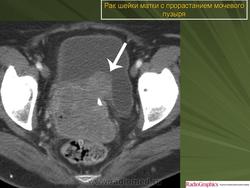

Рак шейки матки

Приложения:

1.rshm_.slayd121.jpg2.rshm_.slayd122.jpg3.rshm_.slayd123.jpg